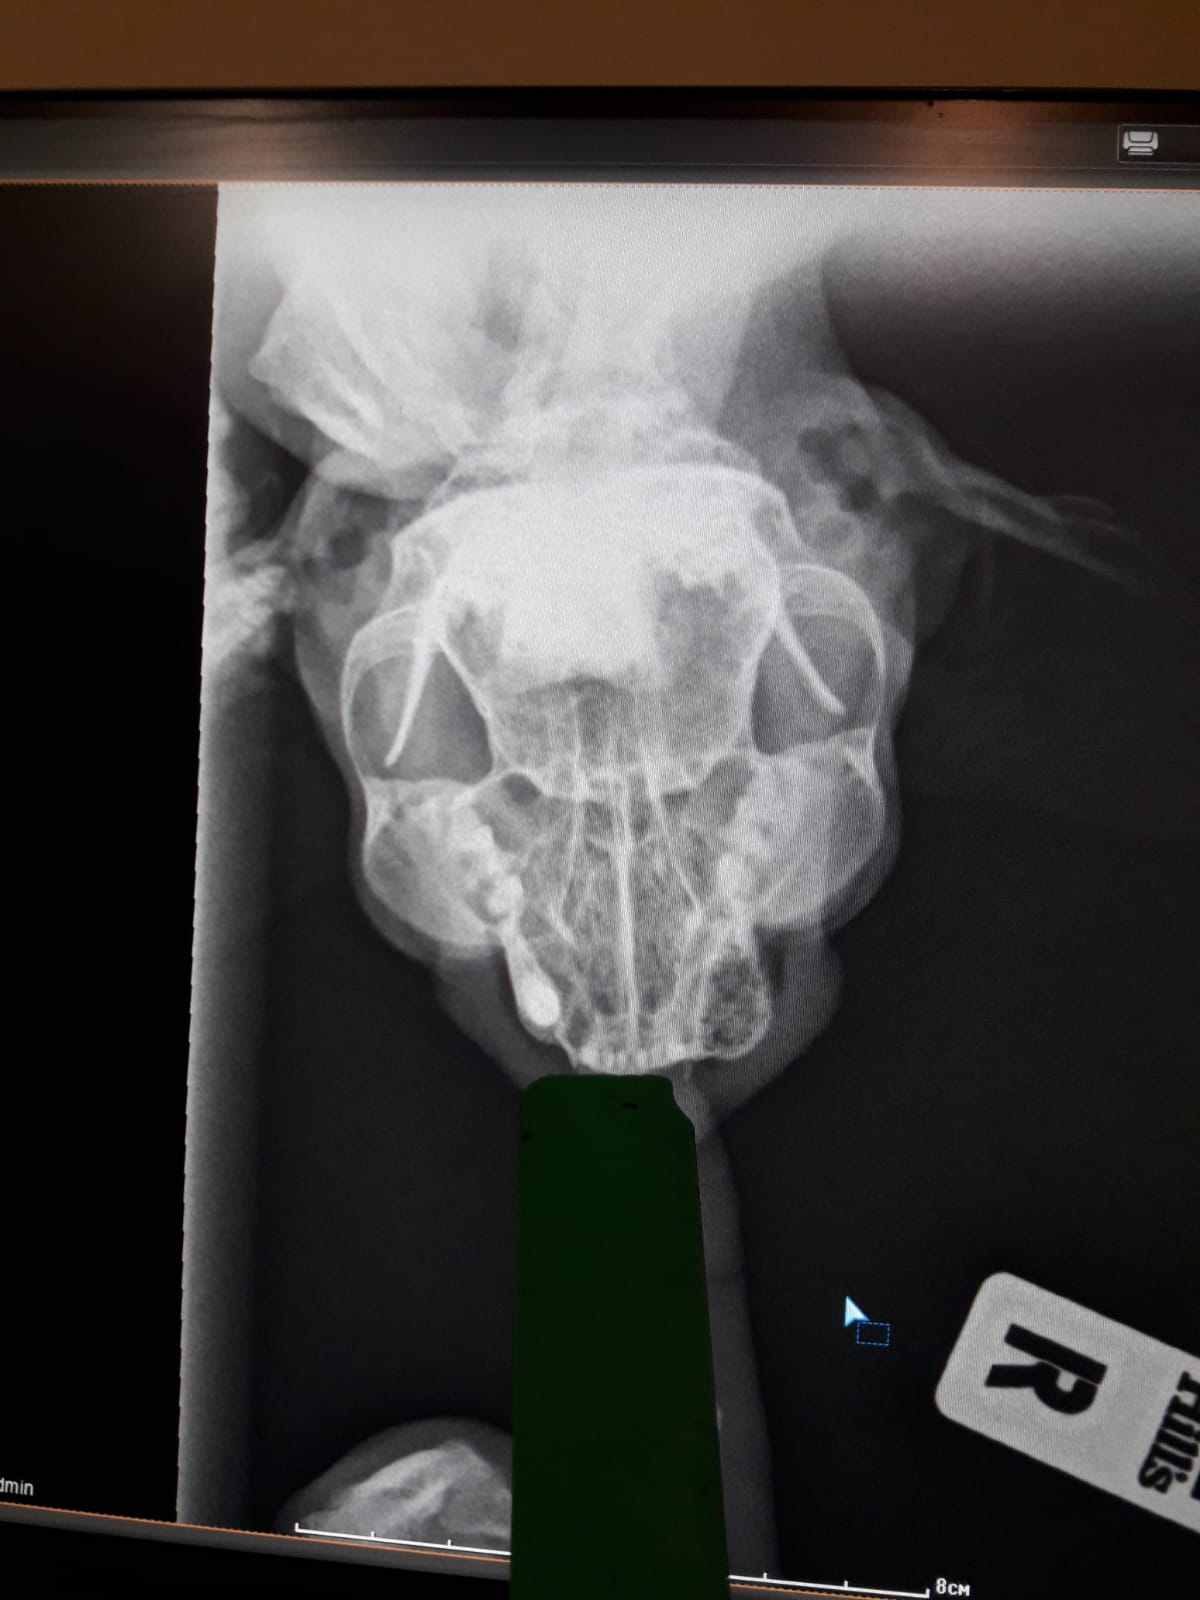

Самое плохое. Под вопросом вялотекущие. Под вопросом онкология, но кость на рентгене не затронута.

На рентгене обвела зону воспаления красным. Очень просим о помощи, одна я кота не вытяну. Девочки, может кто знает, куда, к кому можно стукнуться, попросить сделать пост на поиск финпомощи в соцсетях?